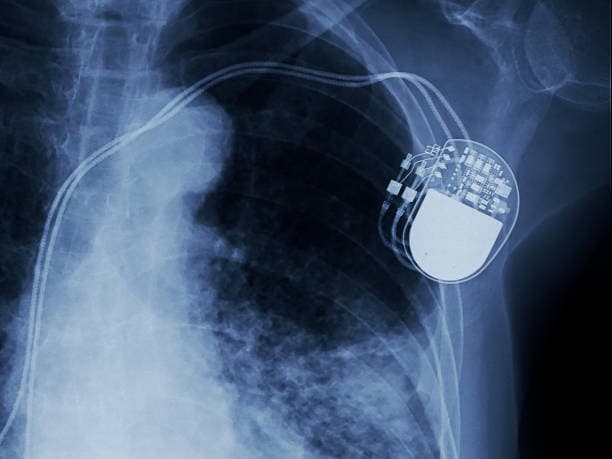

The pacemaker consists of two main components: a pulse generator and one or more leads (wires). The pulse generator is a small, battery-powered unit that produces electrical impulses. It is typically implanted under the skin, just below the collarbone. The leads are thin, flexible wires that extend from the pulse generator to the heart. These leads are threaded through blood vessels and attached to the heart muscle. They transmit the electrical impulses from the pulse generator to the heart, stimulating it to contract at a regular rate.

Modern pacemakers are sophisticated devices that can be programmed to meet the specific needs of each patient. They come in various types, including single-chamber, dual-chamber, and biventricular pacemakers. Single-chamber pacemakers have one lead that is usually placed in the right ventricle, while dual-chamber pacemakers have two leads placed in the right atrium and right ventricle, allowing for coordinated pacing of both chambers. Biventricular pacemakers, also known as cardiac resynchronization therapy (CRT) devices, have three leads placed in the right atrium, right ventricle, and left ventricle, and are used to improve the heart's efficiency in patients with heart failure.